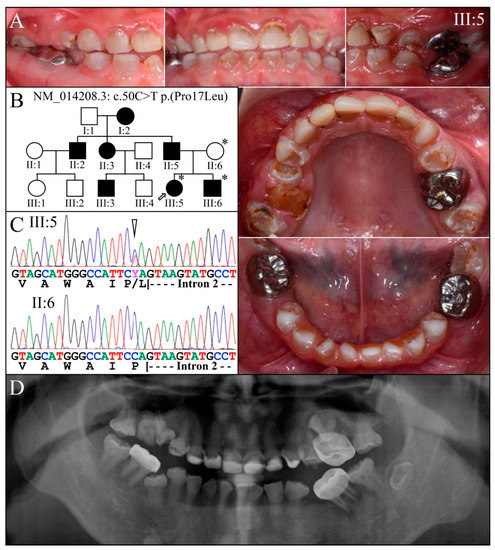

| 5 | Exon 2 | g.7430C>T | c.50C>T | p.(Pro17Leu) | Family 1, [61,62,63] |

| 1 | Illumina HiSeq 2500 (WES) | NG_011595.1:g.7430C>T; NM_014208.3:c.50C>T; NP_055023.2:p.(Pro17Leu) | Missense | II:6, unaffected mother: 136.75× III:5, affected 1st child: 159.3× III:6, affected 2nd child: 129.86× |